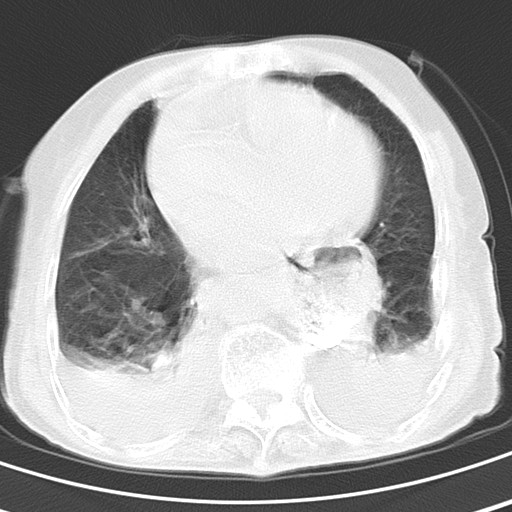

标题: CT21467:女,93岁,摔伤后检查。

女,93岁,摔伤后检查。

右肺炎症,心功能不全伴双侧胸腔积液,右下肺膨胀不全,食管裂孔疝,冠脉钙化,心包少量积液,左侧肋骨骨折,请上传骨窗.

右侧锁骨\\肩胛骨骨折、右侧湿肺,心功能不全伴双侧胸腔积液,右下肺膨胀不全,左膈破裂或食管裂孔疝,冠脉钙化,心包少量积液,请上传骨窗.

右肺炎症,心功能不全伴双侧胸腔积液,右下肺膨胀不全,食管裂孔疝,冠脉钙化,心包少量积液,左侧肋骨骨折,右肩甲骨粉碎性骨折。93岁,高寿哇!

右肺炎症,心功能不全伴双侧胸腔积液,右下肺膨胀不全,食管裂孔疝,冠脉钙化,心包少量积液,左侧肋骨骨折,右肩甲骨粉碎性骨折。